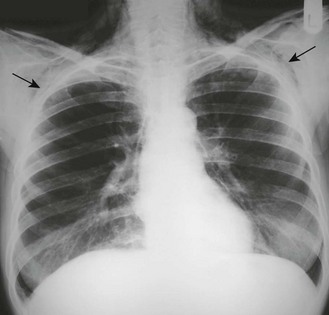

The standard chest X-ray is a posteroanterior (PA) view taken with the film in front of the anterior chest and the X-ray source 2 metres behind the patient (Fig. 7.22). In an anteroposterior (AP) film the X-ray source is in front of the patient, which tends to enlarge anterior structures such as the heart. Always compare an abnormal chest X-ray with previous films to see if abnormalities are resolving or longstanding.